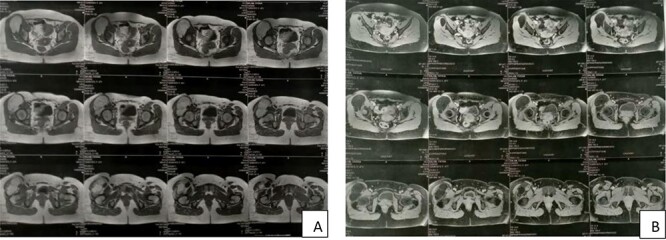

Figure 2.

MRI showing a well-circumscribed mass in high signal intensity on Tl (A) and low signal intensity on T2 (B).